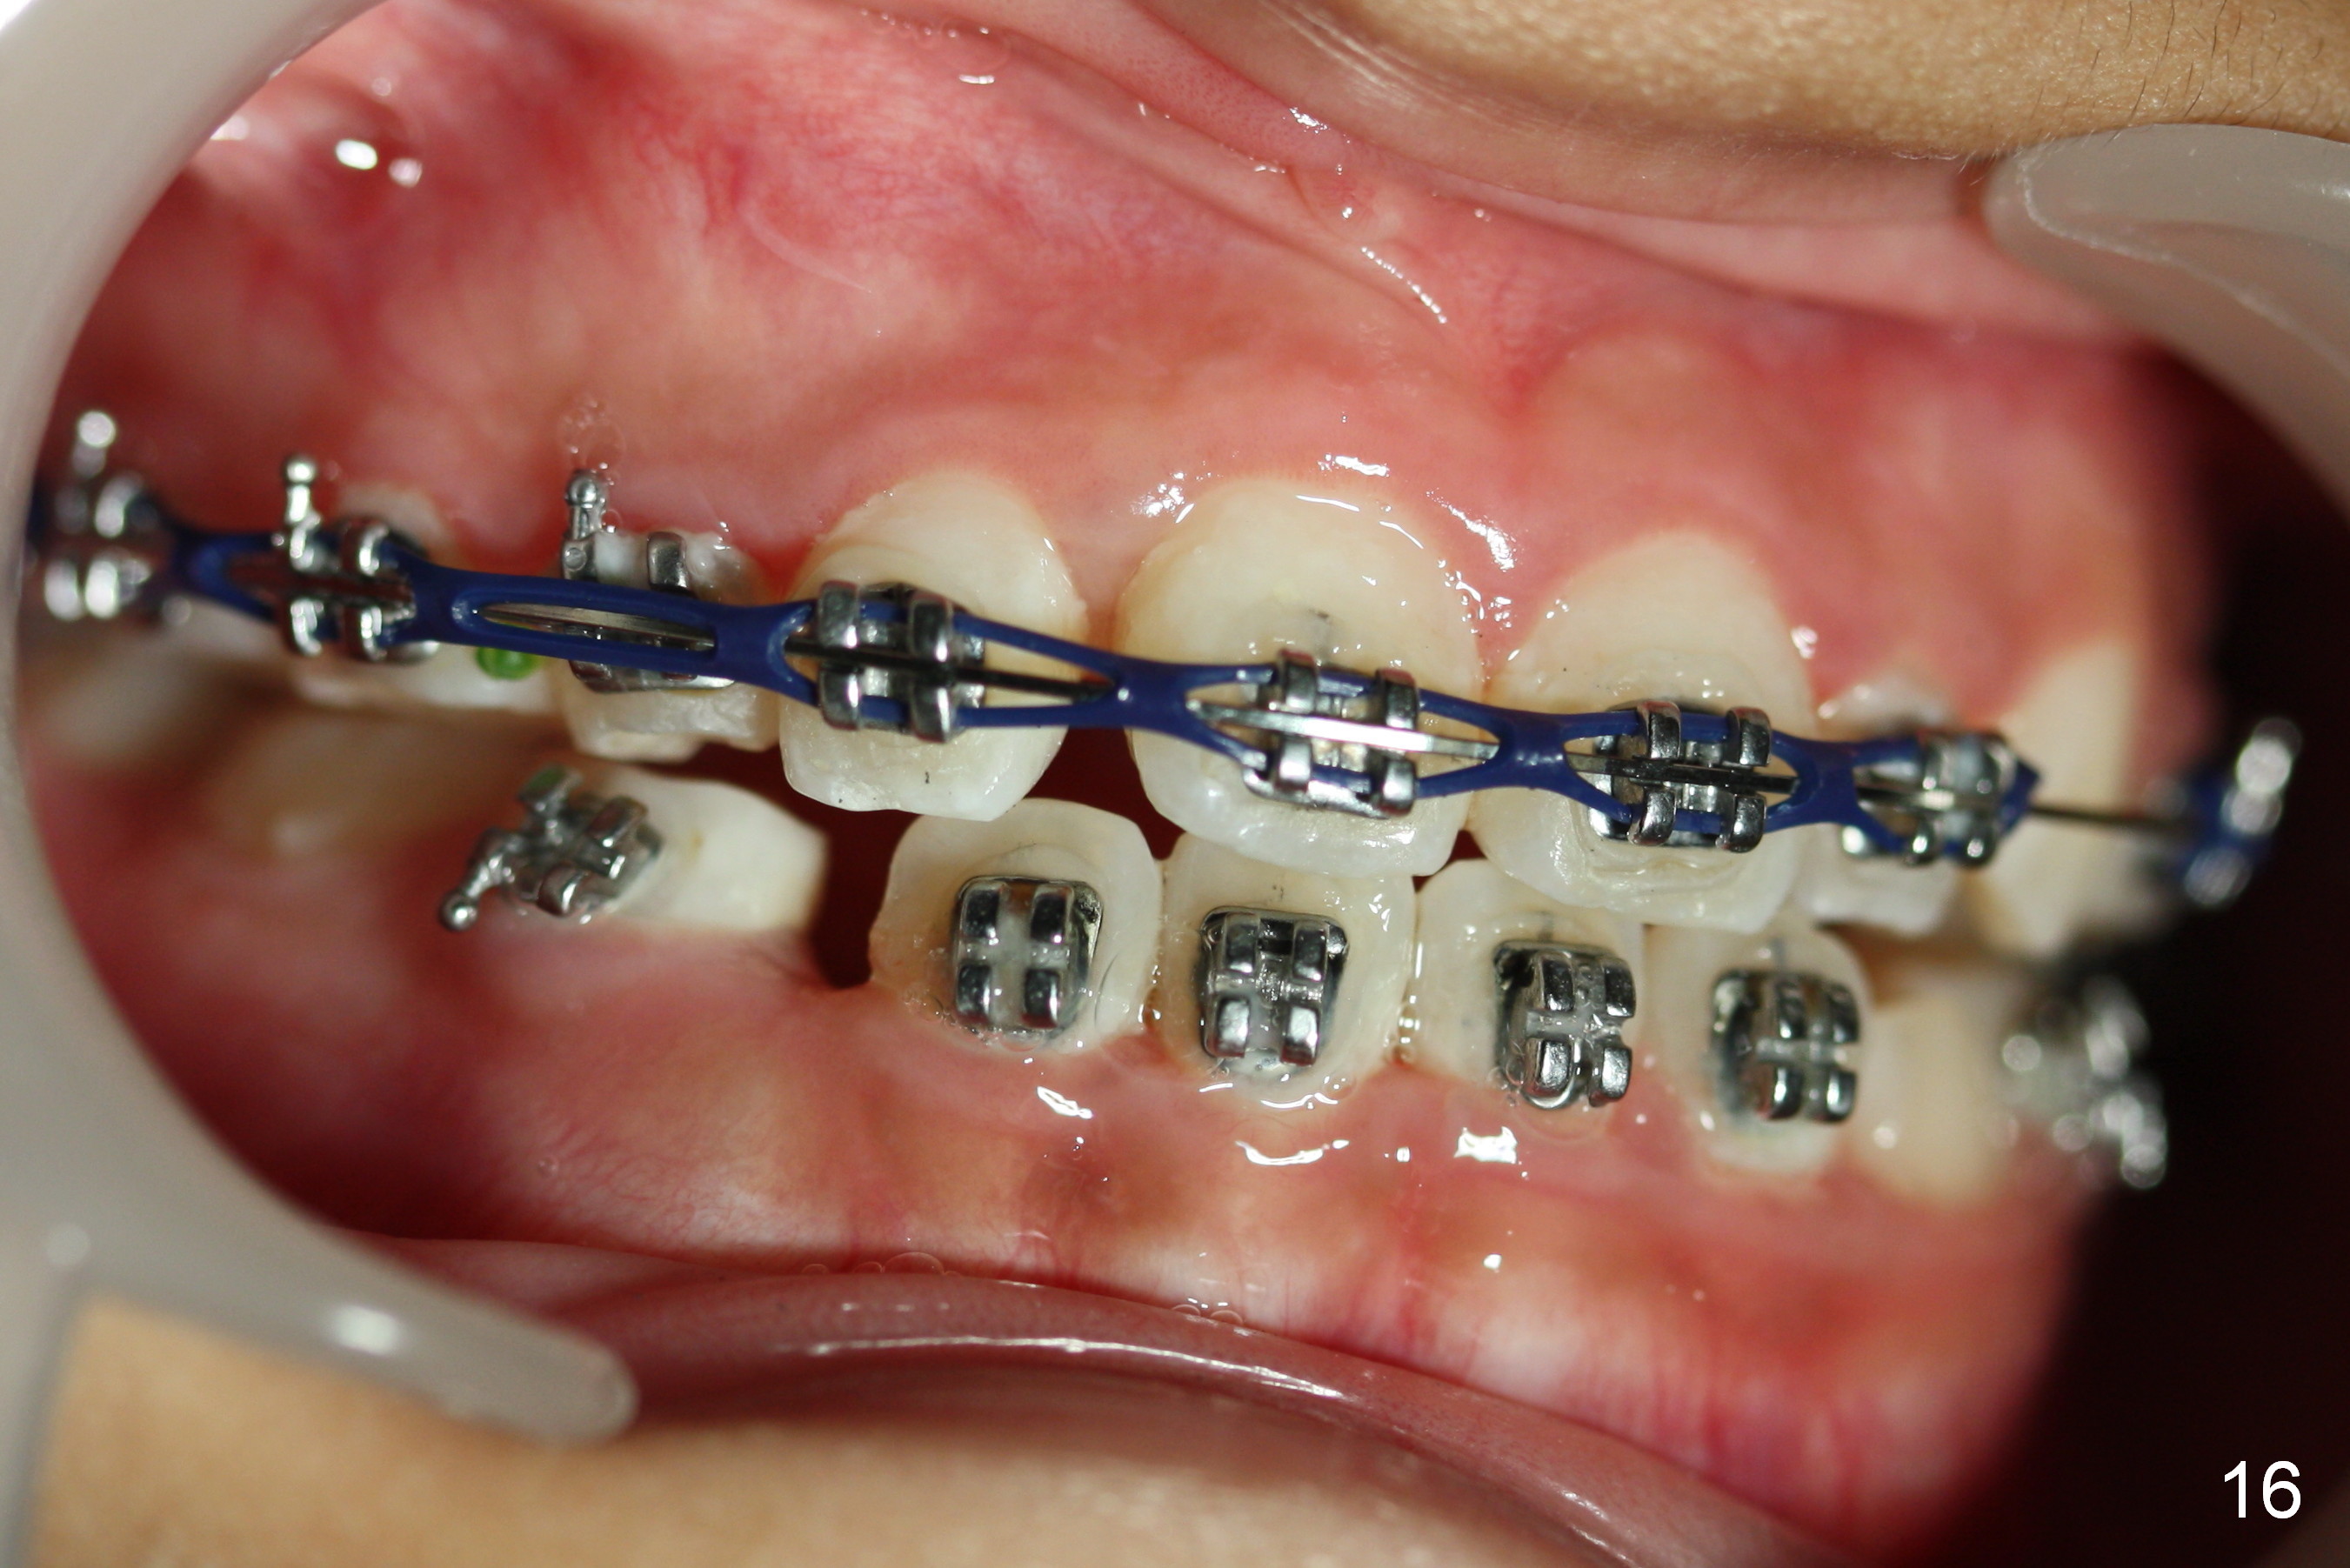

The 2nd visit post bracketing, the lower brackets are placed (Fig.5). The cross bite is still not completely fixed (Fig.6).